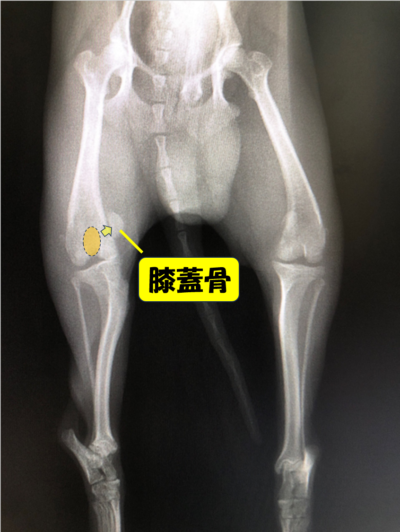

膝蓋骨脱臼(通称パテラ)とは、本来は膝蓋骨(膝のお皿の骨)が大腿骨(太ももの骨)の真正面になければいけないのに、膝蓋骨が脱臼してしまう病気です。

内側にずれてしまうことを内方脱臼、外側にずれてしまうことを外方脱臼といいます。

診断

・触診

・レントゲン検査